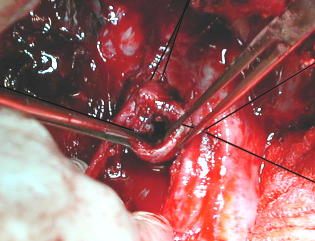

Sección de la traquea

(a)- Incisión transversa en la traquea, distal a la estenosis y colocación de tubo endotraqueal flexible, corrugado y balonado para ventilación, se conecta al tubo de ventilación de la maquina anestésica, se fija y se completa la sección de la traquea.

(b)- El nervio vago en referencia de latex.

Resección de la lesión

Cocluida la seccion de la traquea. El cabo distal intubado y aislado.

Observe el estado de los anillos traqueales proximales, engrosados fibroticos y con obliteración parcial del conducto traqueal.

Se separa la pared mucosa traqueal del esófago en una longitud igual al segmento estenosado y se resecan 3 anillos.